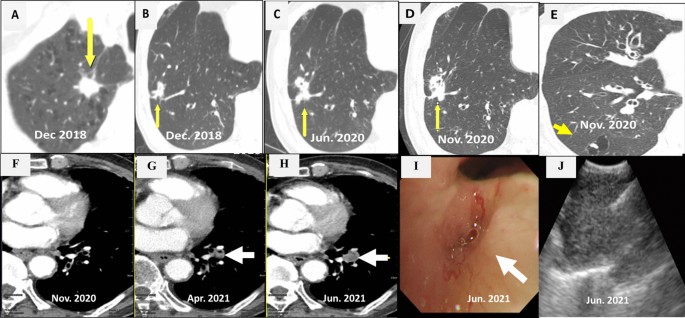

CT scan showed a 1.4 cm × 1.3 cm mass in the right upper lobe (RUL) (Fig. 1 a) and a right lower lobe (RLL) mass-like consolidation (Fig. 1 b). Histopathologic examinations of CT-guided-percutaneous needle biopsy (PCNB) of the RUL mass revealed adenocarcinoma (ADC) (Fig. 2 a–c) with clinical staging cT1bN0M0 on ultrasonic-guided transbronchial needle biopsy (EBUS-TBNB) and fluorodeoxyglucose F18-positron emission tomography (FDG-PET) scan. RLL mass showed no metabolism on the FDG-PET scan. The FEV 1 was 56% of the predicted value. We planned a lobectomy for the RUL cancer and a follow-up for the RLL mass. However, the patient refused to undergo surgery and was treated with stereotactic radiosurgery (SRS) on the RUL mass in January 2019. The RLL mass-like consolidation did not show any changes on the follow-up chest CT or FDG-PET scan in November 2019.

Chest CT scans. a A mass on the RUL of the first adenocarcinoma (arrow). b A mass on the RLL at the same time of the first cancer diagnosis (arrow). c Increased RLL mass six months later (arrow). d Further increased RLL mass after five months (arrow). e New nodule on the peripheral RLL (arrow). f–h Development and increase of the lymph node (arrow). i Bronchoscopic finding showing LLL anterobasal segment obstruction (arrow). j Lymph node enlargement on the EBUS. CT, computed tomography; RUL, right upper lobe; RLL, right lower lobe; LLL, left lower lobe; EBUS, endobronchial ultrasound

In June 2020, the RLL mass-like consolidation was found to have increased on a chest CT scan (Fig. 1 c). PCNB of the RLL mass was performed, and histologic examination revealed anthracofibrosis. Five months later, the RLL mass increased further (Fig. 1 d), and a new nodule appeared at the periphery of the RLL (Fig. 1 e). PCNB was performed again on the same RLL mass (Fig. 1 d), and histological examination demonstrated squamous cell carcinoma (SCC) (Fig. 2 d–f). There was no metastasis except for hypermetabolism of the new nodule in the RLL periphery (Fig. 1 e) on the FDG-PET scans. We could not perform a biopsy for the new peripheral nodule (Fig. 1 e) due to cystic changes. We concluded the clinical staging of the RLL SCC as cT3N0M0 on the EBUS-TBNB and PET scan. SRSs were performed separately for the RLL SCC and the new RLL peripheral nodule, respectively in February 2021.

We performed chest CT scan for surveillance of lung cancer. Five months later after 2nd SCC diagnosis, a new nodule emerged at the left lower lobe (LLL) (Fig. 1 f, g). Two months after that, the nodule increased further (Fig. 1 h). Bronchoscopy showed new total obstruction of the anterobasal segmental bronchus of the LLL (Fig. 1 i). Histologic examinations of bronchial biopsy and EBUS-TBNB (Fig. 1 j) for LLL lesions demonstrated small cell lung carcinoma (SCLC) (Fig. 2 g–i). Clinical staging was limited stage. The patient was treated with chemotherapy (etoposide/carboplatin) and concurrent thoracic radiation.